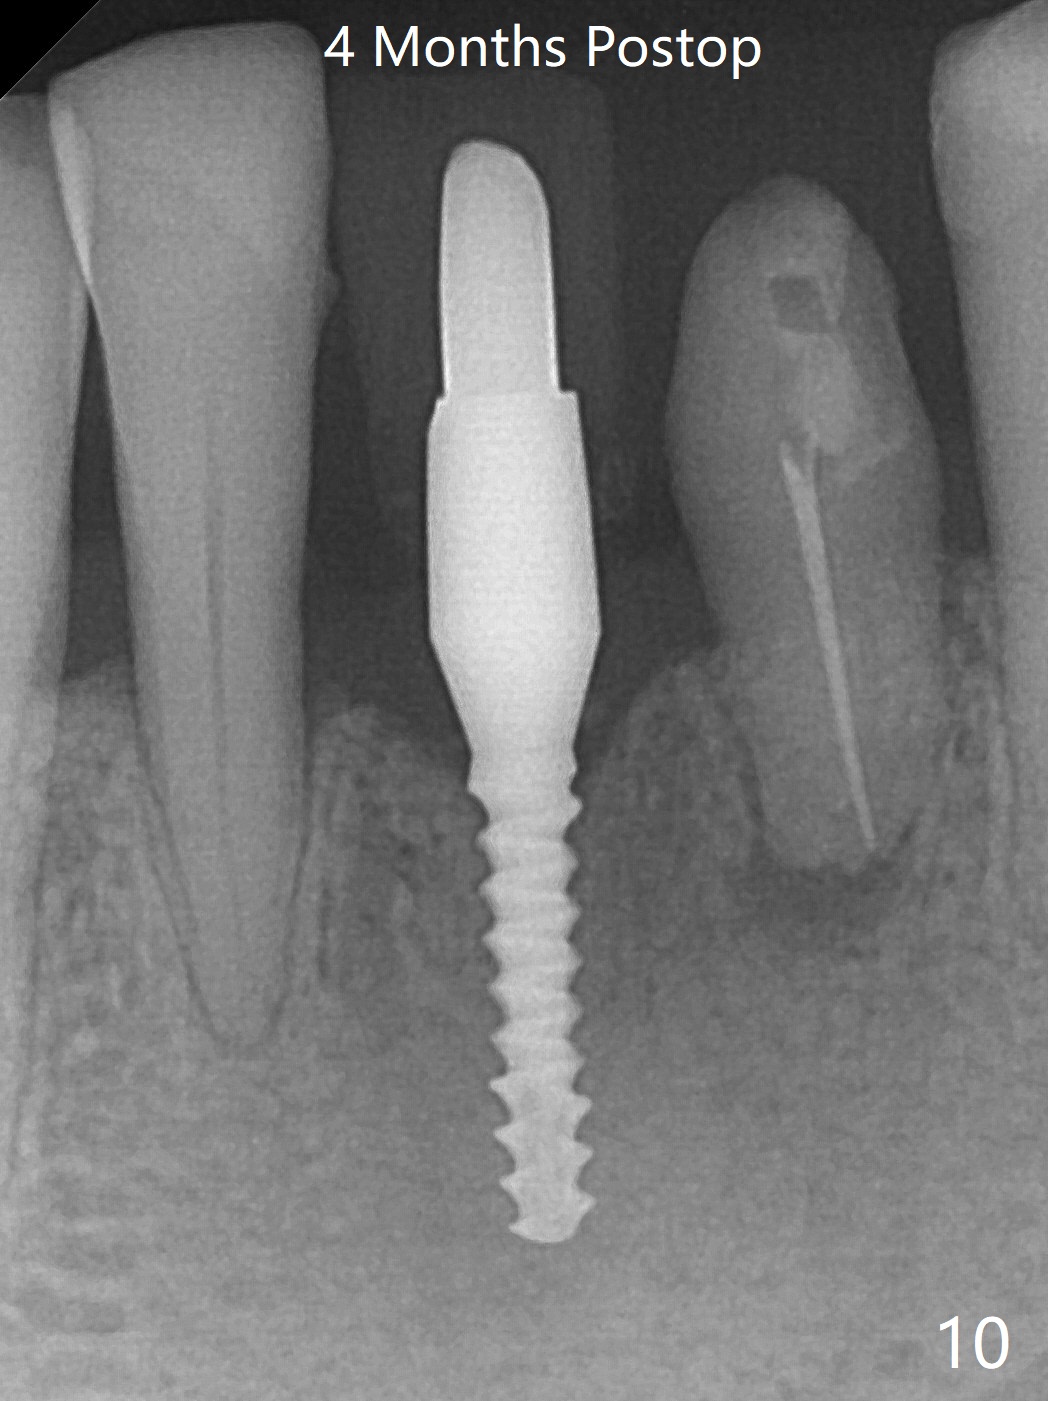

左下第一磨牙(#19)牙槽嵴狭窄,2.2毫米钻头完成导板钻洞后,舌侧骨板开始破裂(图一:<),打消牙槽嵴劈开术念头,放置2.5x8.5毫米一段式植体(图二(8.5毫米是最短植体)),好像离下齿槽神经管还有一定距离,适当植入深些(图四:箭头,15Ncm)。右下中切牙缺牙区牙槽嵴也十分狭窄(图四),最后不得不徒手植入2x8.5毫米植体(图五,六,25Ncm)。如果按设计植入2x12毫米植体,颊侧,或者舌侧骨板更容易穿孔。术后3.5月牙槽嵴下降(图七:箭头),可能术中那里压力太大,今后牙槽嵴钻洞要大。24号牙根尖阴影(图七),完成根管治疗(图八)。19牙位牙槽嵴吸收也严重(图九)。其实术后4个月19牙位牙槽嵴吸收并不严重(图十一)。